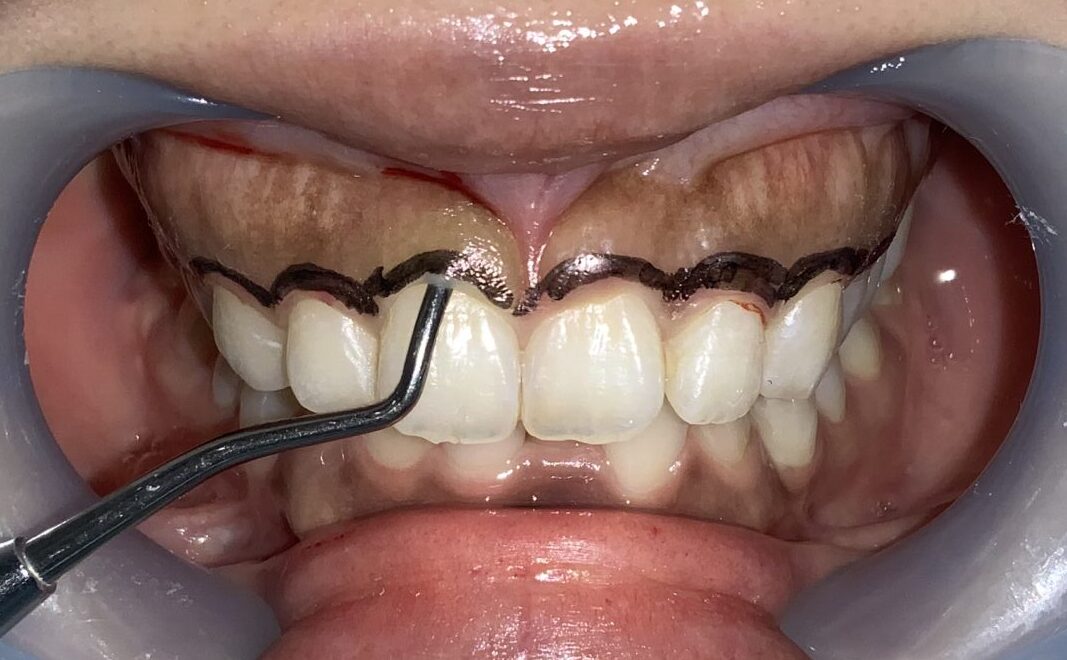

検査結果から、歯ぐきの切除範囲をマーキングして、もう一度検査データと切除範囲の間違いがないかを確認します。

切除範囲の設定は完璧です。